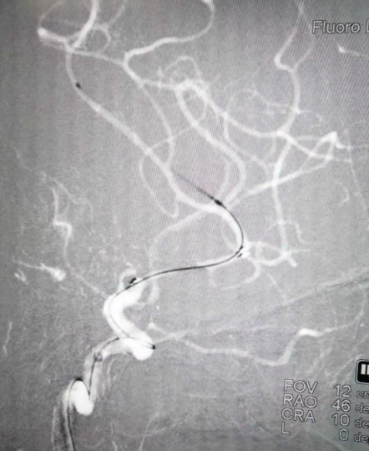

药物球囊扩张(2.0 mm×20 mm)

药物球囊扩张后

药物球囊扩张后10分钟狭窄明显改善且血管壁较光滑

扩张前带涂层的球囊(左图)与扩张后释放完涂层的球囊(右图)